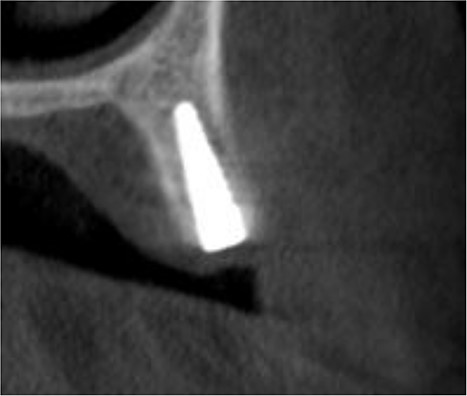

Under local anesthesia with 4% articaine solution, a full-thickness flap was raised to expose the alveolar ridge. The initial point was marked with a point drill. The implant site was first prepared with a 2.2 mm pilot drill, and then with a 3.3 mm drill. After preparing the implant bed, we noticed the disappearance of the coronal and middle third of the buccal wall, exactly as planned. A submerged implant system (INNO submerged implant; Cowellmedi Inc, South Korea) was inserted according to the manufacturer’s instructions (Fig. 1). The insertion torque value was 33 N.cm. several perforations were prepared at the buccal side of the recipient bone bed using a small round bur for better blood supply. An allogeneic bone graft material (Cortical Cancellous powder; TRCIR Co, Iran) was used to reconstruct the buccal plate. A prefabricated L-shaped titanium mesh has been adapted to fit the shape of the alveolar ridge to be reconstructed, and it was fixed to the implant with a cover screw (Fig. 2). The flap was mobilized to permit a tension-free primary closure, was closed with 4–0 silk sutures. Sutures removal was done after 1 week. The surgical sites were left to heal for 6 months.

Inserting a dental implant of 3.5 mm diameter and 10 mm length into its prepared bed. The implant was completely surrounded by bone in its apical third only.

Reconstruction of the buccal plate using an allogeneic bone graft material and a prefabricated L-shaped titanium mesh. The titanium mesh was fixed to the implant with a cover screw.